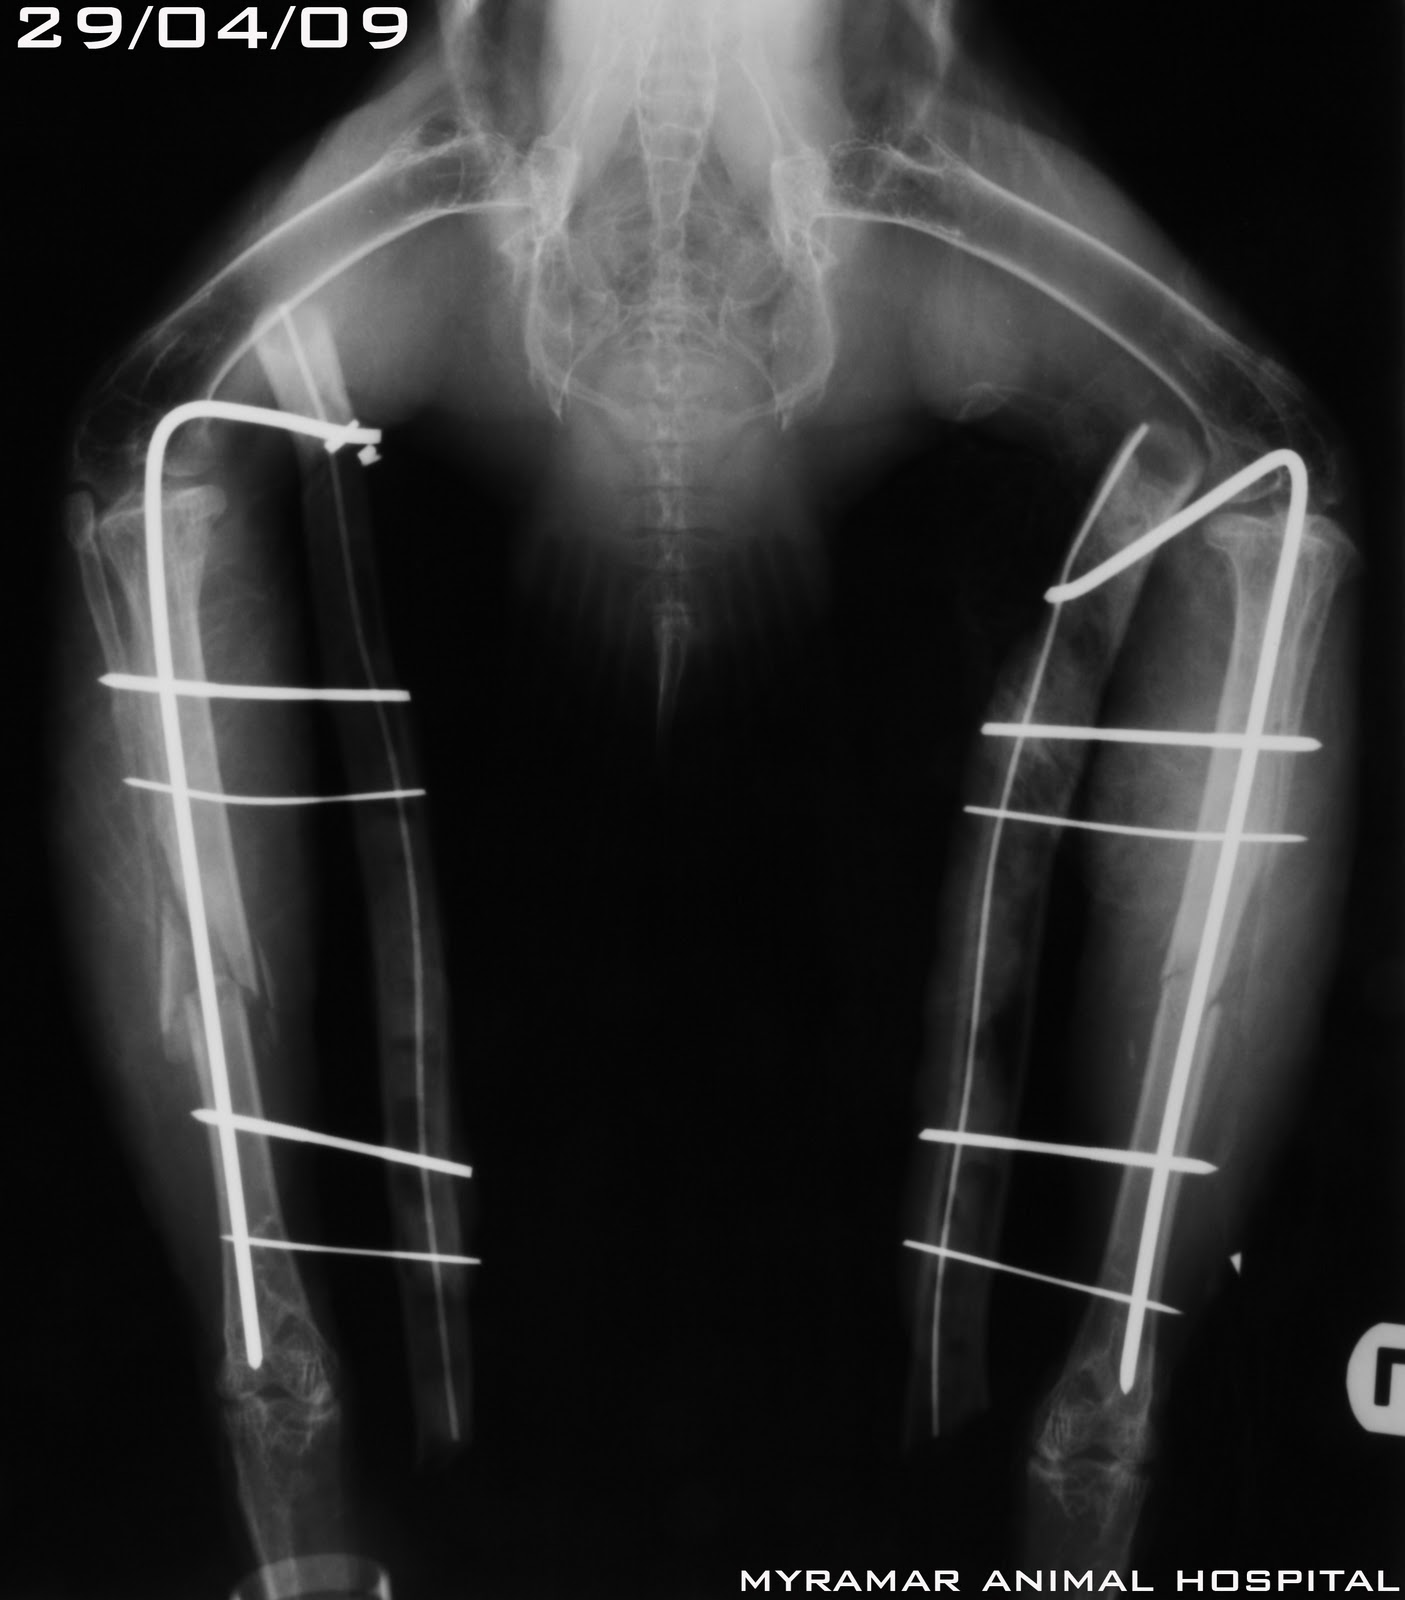

Chico, Aguila real de 1 año y 3,5 kg es referido al Myramar Animal Hospital de Fuengirola con

fractura bilateral tibial tras un accidente cuando volaba. Class AOVET:42-A3 y 42-B1. Ambas fracturas se reducen y estabilizan utilizando técnica Tie-in utilizando PMMA como conector de agujas.

Se presetan radiografías pre y postoperatorias así como evolución de la cicatrización ósea